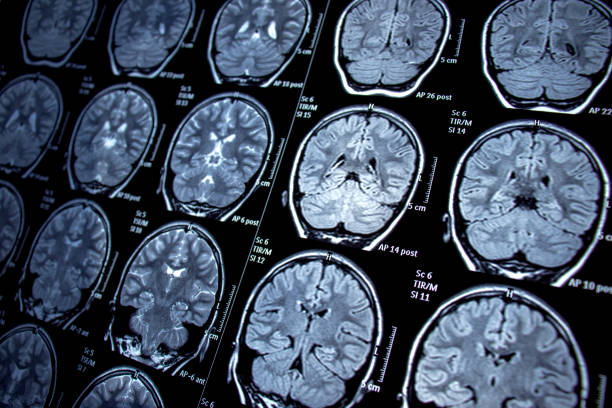

- 技術助力定位:隨著功能性磁共振成像(fMRI)等先進成像技術的發展,外科醫生能夠定位癲癇區域,并確定大腦相應區域手術可能導致的術后缺陷。

- 預后較好情況:MRI 上具有電臨床一致的結構性病變的患者預后最好,60% 至 70% 的病例癲癇發作能減少。

- 預后較差情況:患有顳葉外病灶、局灶性至雙側強直陣攣性癲癇、影像學正常、精神合并癥以及學習障礙的患者通常手術成功率較低。